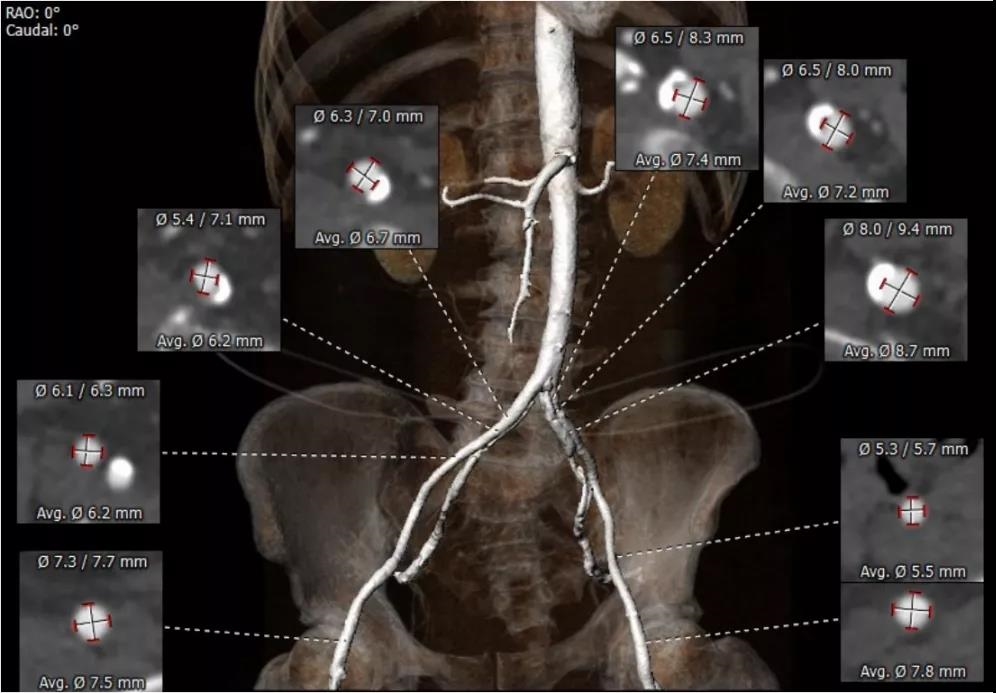

患者男性,77岁。术前心脏超声提示主动脉瓣钙化,重度狭窄,轻度反流。CT评估结果显示主动脉瓣为Type-1型二叶瓣,瓣叶增厚钙化,瓣环平均直径23.4mm,瓣环面积428.0mm²,面积径23.3mm。左冠脉开口高度19.6mm,右冠脉开口高度13.9mm。术前经详尽影像学重建、评估及病例讨论,测量瓣环直径,评估冠脉梗阻风险后,计划植入23# Renatus介入主动脉瓣。

外周血管评估